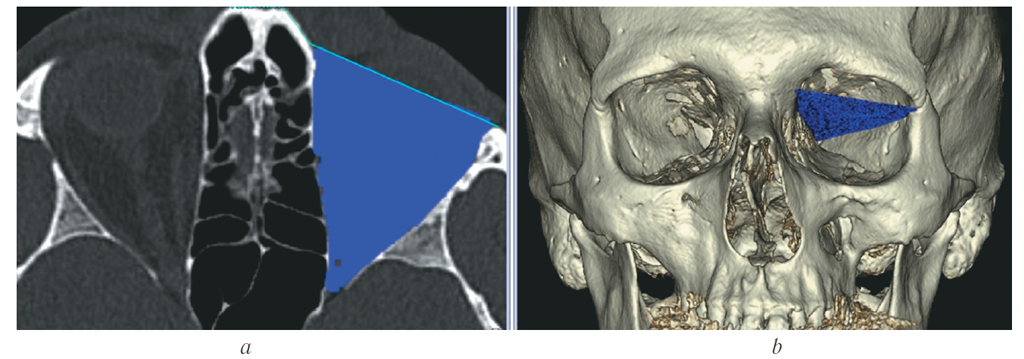

- На изображениях определяли костные границы орбит, по которым будет проходить маркировка. Необходимым условием правильного выполнения исследования является симметричность костных границ для обеих орбит. Для определения наружной границы маркировки проводили линию через всю длину орбиты и перпендикуляр к её длине (построения выполняли сразу для обеих орбит) (рис. 1).

Рис. 1. МСКТ, средняя зона лица, костный режим. Аксиальная реконструкция. Определение наружных границ обит

Fig. 1. MSCT, midface, bone window. Аxial reconstruction. Marking of orbital bone borders

- На каждом аксиальном срезе выполняли маркировку всех костных границ орбит, начиная с верхней стенки до уровня дна орбиты (рис. 2). Для точности измерения необходимо чётко соблюдать костные границы и учитывать анатомические вариации строения, а также участки повреждения целостности стенок орбиты.

Рис. 2. МСКТ, средняя зона лица, костный режим. Аксиальная (a) и 3D-реконструкция (b). Маркировка костных границ орбиты

Fig. 2. MSCT, midface, bone window. Аxial (a) and 3D (b) reconstruction. Marking of orbital bone borders